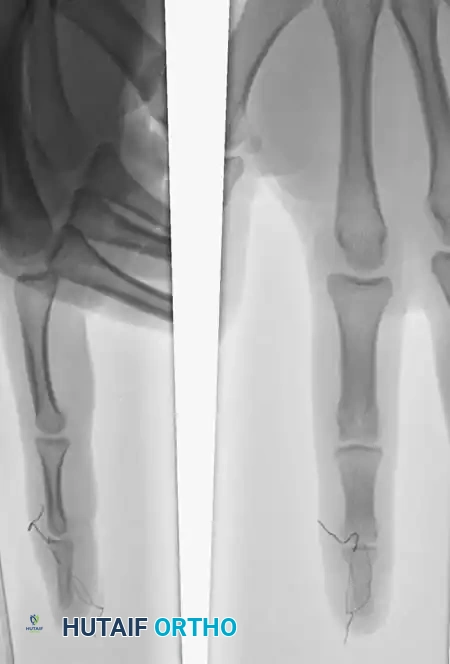

Clinical Case Example

The efficacy of the pull-out wire technique is demonstrated in the management of high-demand athletes.

Fig. 64-65 A, Type 4 mallet fi nger in high school basketball player. B, Results of pull-out wire and pin fi xation of distal interphalangeal joint just before pin removal at 4 weeks. C, Pull-out wire left in until 6 weeks after surgery.

In this scenario, a Type 4 mallet finger in a high school basketball player (A) was treated with pull-out wire and pin fixation. The transarticular pin is typically removed at 4 weeks (B), allowing early protected motion, while the pull-out wire is maintained until 6 weeks postoperatively (C) to ensure solid bony union of the avulsed fragment.